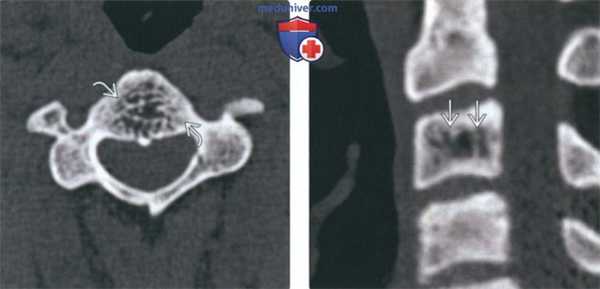

(Слева) На аксиальной КТ без КУ визуализируется относительно хорошо отграниченный участок без склеротического ободка. Ключевые диагностические признаки: «жировая» плотность и картина «пчелиных сот».

(Справа) На сагиттальной реформатированной КТ определяется гиподенсный участок в теле СЗ с немногочисленными утолщенными трабекулами, ориентированными вертикально (характерные КТ-признаки гемангиомы позвонка). Вертикальные трабекулы не всегда соединяют обе замы кегельные пластинки.